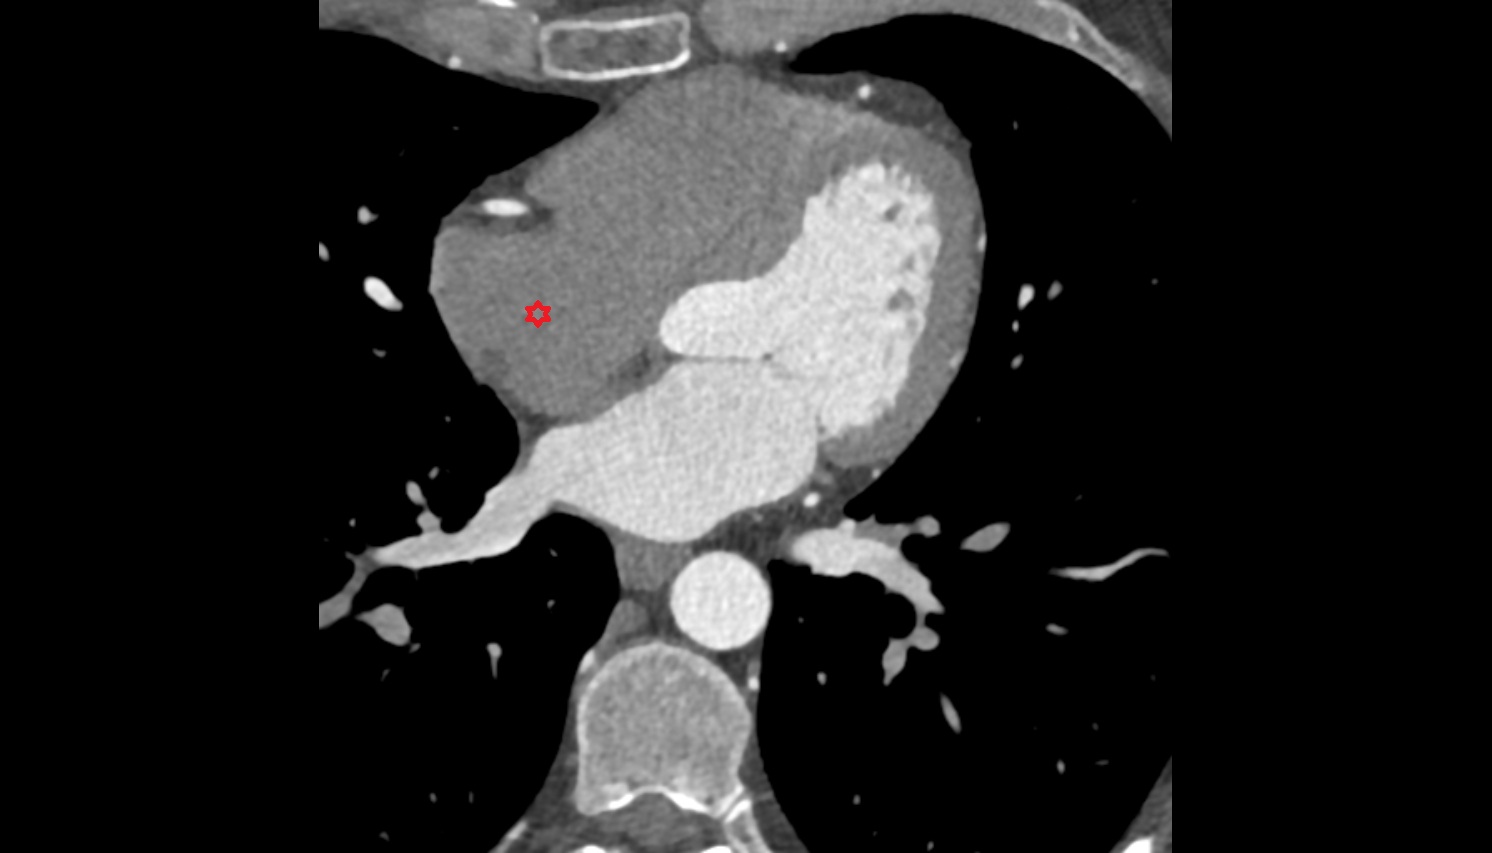

- Heart

- Left ventricle

- Right atrium

- Left atrium

- Right ventricle